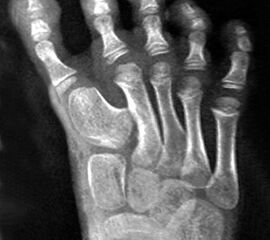

Symptomatik

Klinisches Erscheinungsbild eines Hallux varus (eigenes Bildmaterial)

Abbildung 1

Bei einer geringgradigen Ausprägung eines Hallux varus (bis ca. 10° negativer Hallux-valgus-Winkel) sind die Betroffenen selten beeinträchtigt, in der Regel bedarf es keiner Therapie. Die Korrektur durch den Druck der Zehenkappe im Schuh ist meist bereits ausreichend.

Bei zunehmender Fehlstellung klagen die Patienten über Druckbeschwerden im Schuh, insbesondere am Endglied innenseitig oder über dem IP-Gelenk der Großzehe sowie über bewegungsabhängige Schmerzen im 1. MTP-Gelenk. Häufig sind die Betroffenen auch kosmetisch unzufrieden (Janis et al., 1975).